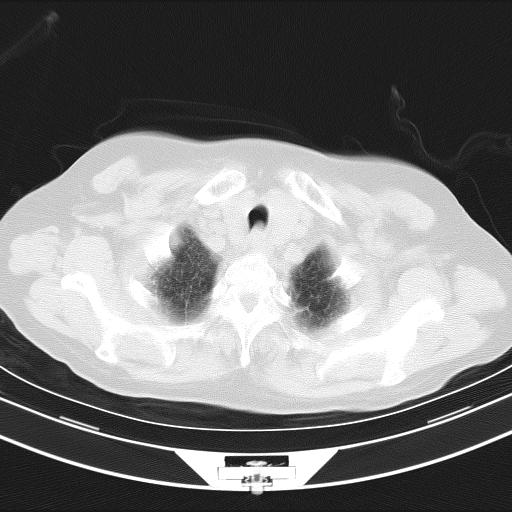

老年女性,嗜睡3天,意识模糊。轻咳,无发热。

两肺慢支炎伴感染,左侧胸腔积液。纵膈及双侧肺门淋巴结肿大建议复查。

双肺多发淡片影,毛玻璃影,,支持支气管肺炎,,建议血气找原因,,嗜睡是否肺性脑病?有没有慢支病史?

1)两肺感染性病变;建议抗炎治疗后复查。2)纵隔淋巴结肿大。3)左侧胸腔积液。